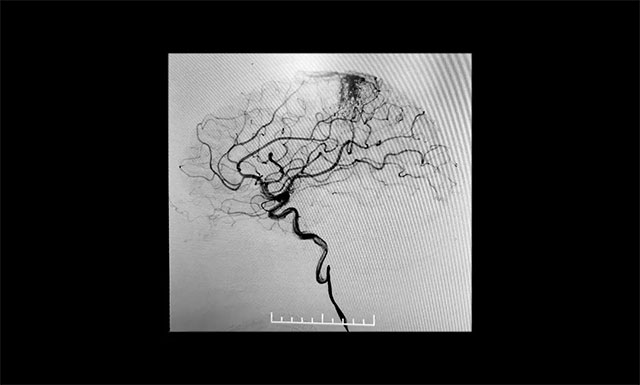

▲ DSA检查显示,中央后回动静脉畸形

患者为55岁男性,4月份突发右眼失明,头颅CT+CTA显示,左侧顶叶异常强化灶,考虑血管畸形AVM可能。经医院DSA检查,确诊为功能区动静脉畸形,畸形团分布较弥散,位于中央后回,主要由大脑前动脉分支供血,通过皮层静脉向上矢状窦引流。该患者畸形血管团体积较大,且与其相连的供血动脉及回流静脉交织纷乱、复杂、异常粗大,病灶紧邻运动中枢、语言中枢、书写中枢等重要结构。

张琪博士团队制定了严密的手术计划,预料各种术中、术后可能出现的意外及并发症。7月12日行动静脉畸形介入栓塞术,术中导管在动静脉畸形部位缓慢推注Onyx18生物胶,DSA透视下显示胶在畸形中弥散良好,无明显反流,顺利栓塞。